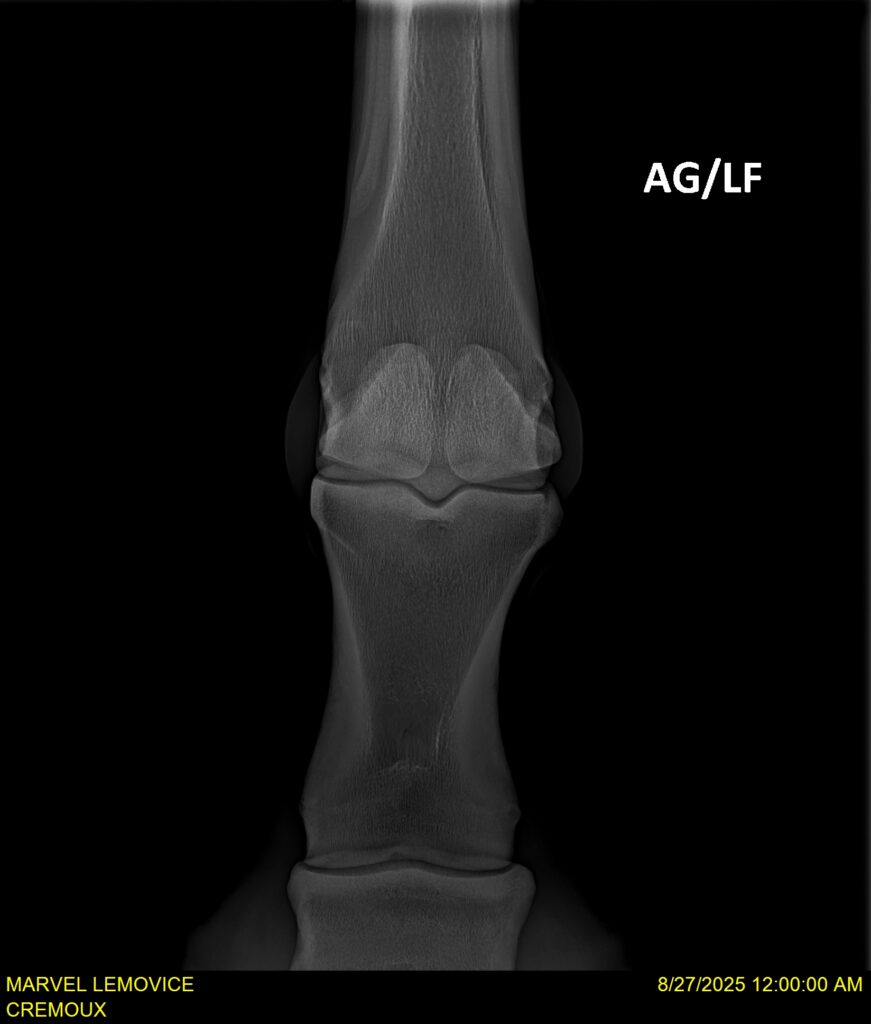

MARVEL LEMOVICE, hongre, Selle Français prend 4 ans en 2026. POPSTAR LOZONAIS x ROSIRE sur une excellente souche maternelle de l’élevage PLATIERE. Débourré aux trois allures et mise en route à l’obstacle. Super modèle avec du cadre et de la force, cheval respectueux avec des moyens. Très agréable au quotidien. Transport OK, maréchalerie OK, santé RAS, Bilan 20 clichés radios + clinique OK.

RADIOS ET CLINIQUE